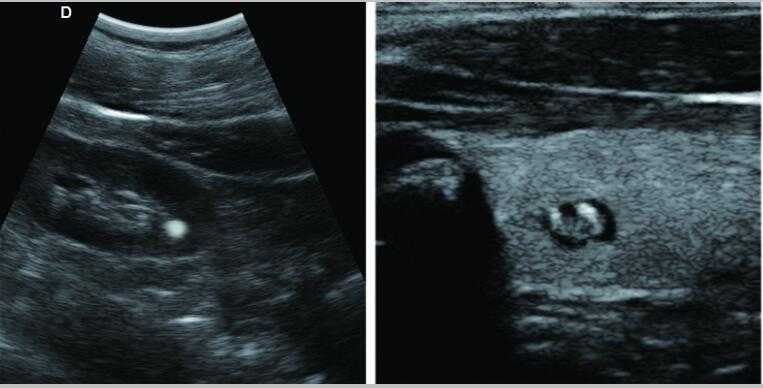

s6獸用B超機

L3-VET筆記本式獸用B超機

L3-VET便攜筆記本式獸用B超機適用探頭

S6便攜筆記本式獸用B超機適用探頭